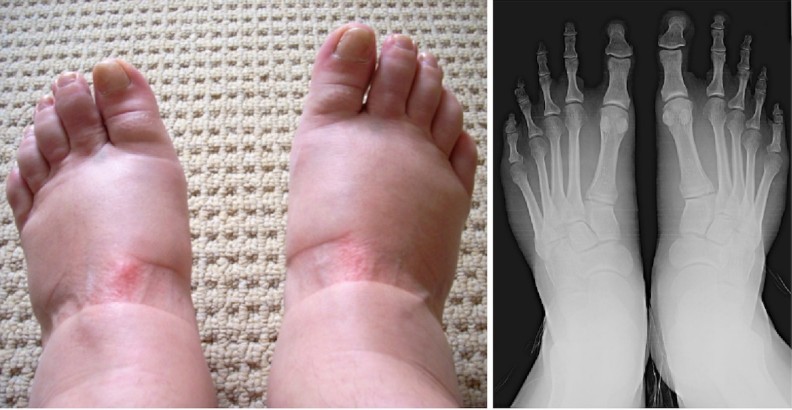

If your legs are swollen and the swelling is accompanied by pain, you should not underestimate your health condition and you should see a doctor. These symptoms can have various causes and it is not possible to rule out, for example, changes in hormone levels, inflammations, damage to the skeletal system, varicose veins or infections.